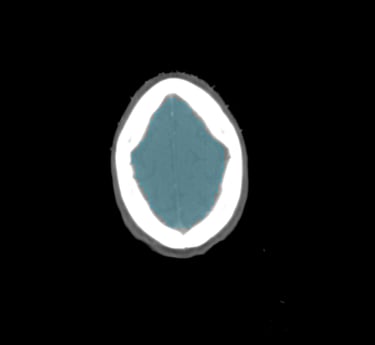

Extensive Structure Library

The DAM Contour features a comprehensive collection of OARs and CTVs that are ready for immediate use, without the need for manual creation of atlases or manual adjustment of data. This product includes all standard OAR and CTV structures (over 117 in total).